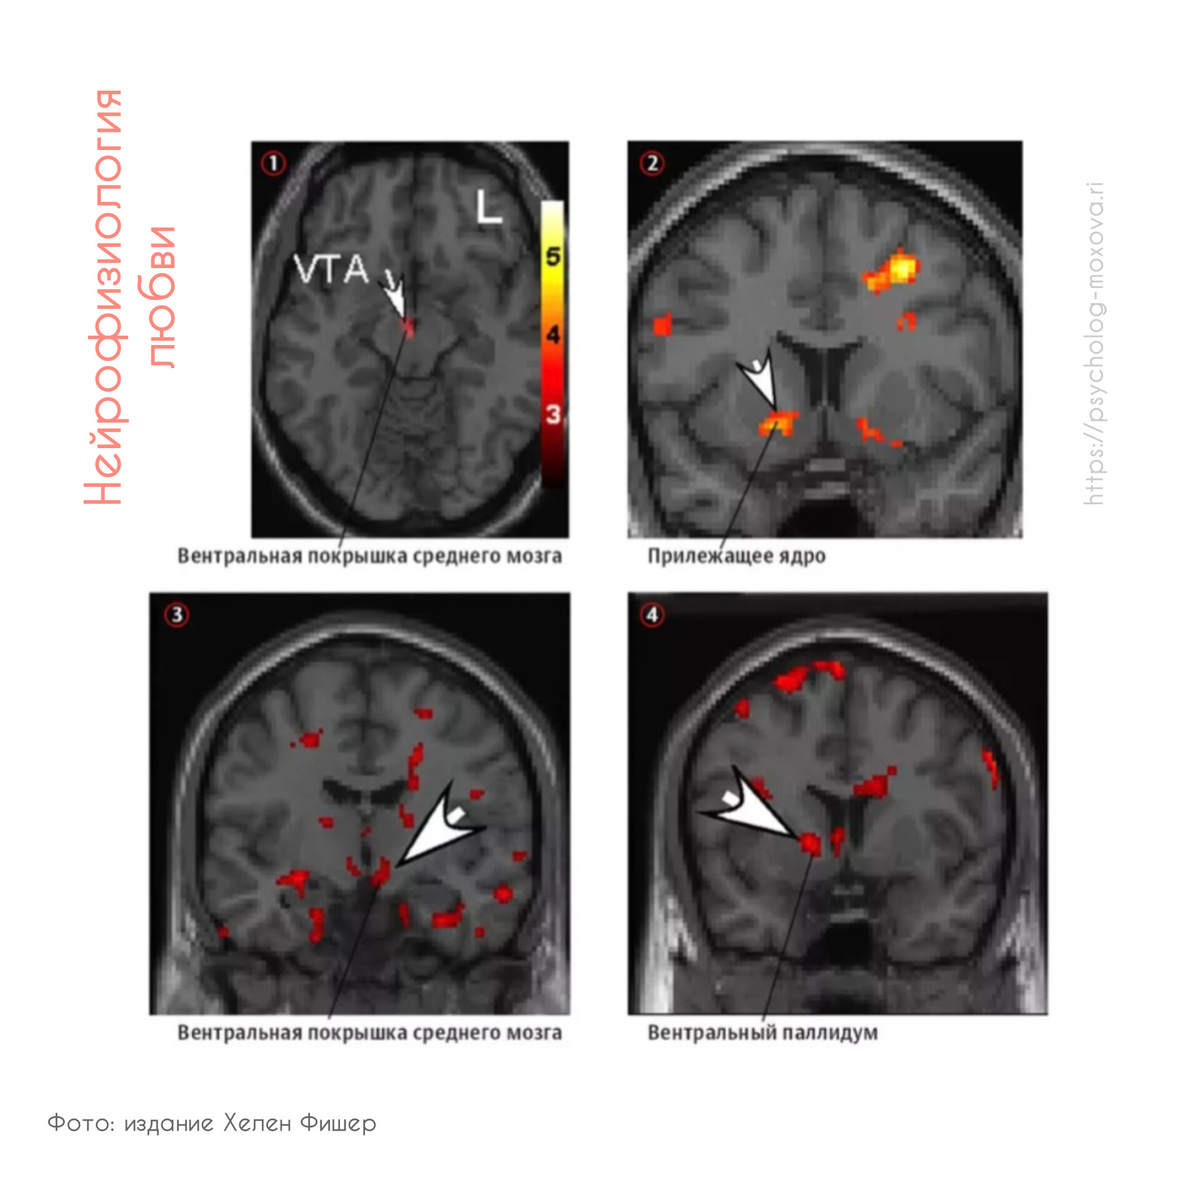

На основе МРТ-изображений исследователи обнаружили, что определенные участки мозга, ответственные за любовь, находятся под управлением дофаминовой системы. Важные компоненты этого механизма включают:

- Вентральная покрышка среднего мозга (ВТА)

- Хвостатое ядро

- Стриатум

- Медиальная префронтальная кора

Роль различных участков мозга

Медиальная префронтальная кора помогает оценить потенциального партнера и его социальные качества, в то время как хвостатое ядро обрабатывает чувства влечения и романтической любви. В вентральной покрышке синтезируется дофамин, играющий ключевую роль в запуске влечения и страсти. Это реакция ведет к ярким эмоциям, повышенной энергичности и сосредоточенности на объекте любви.

К числу других нейромедиаторов, участвующих в этом процессе, относятся серотонин и тестостерон. Интересно, что, согласно исследованиям Фишер, среди супружеских пар, счастливо проживающих более 20 лет, активируются не только структуры, связанные с романтической любовью, но и зоны, отвечающие за счастье, как, например, вентральный паллидум.